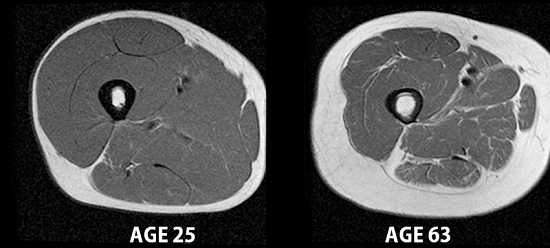

Maintaining muscle is important for strength and mobility in older adults, and muscle cells also burn more calories than fat cells. But muscle protein synthesis slows over time, while the rate at which unexercised muscle degrades stays about the same. This means that older adults lose muscle more easily than younger adults.

Black and white cross-sections of two human thighs. The one labeled 'age 25' has more muscle and less fat than the other labeled 'age 63'. MRI images of a 25-year-old man and a 63-year-old man’s upper thighs, showing skeletal muscle (dark gray), fat, and bone. Credit: Carl Murphy and Sheri Coker, University of Alaska Fairbanks.

To prevent muscle loss, older adults need to consume enough essential amino acids, components of proteins that help build muscle. However, doctors often recommend weight loss through diet to those who are overweight or obese to help reduce health risks. And getting enough essential amino acids through a reduced-calorie diet can be difficult and can result in muscle loss.